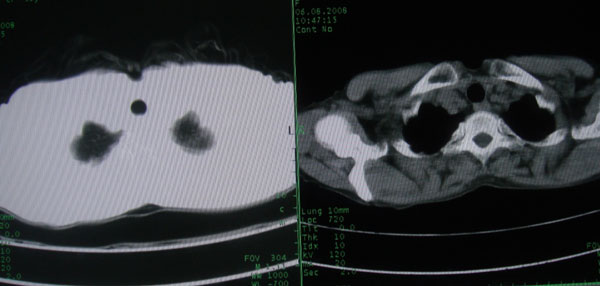

标题: CT15046:F59Y,咳嗽间断咳血丝痰就诊. [打印本页]

咳嗽\间断咳血丝痰就诊.

1慢支伴感染;右下肺周围型肺癌。

多考虑支气管扩张并感染,双下肺继发性肺结核不除外

周围型肺癌征象不明显,应不予首先考虑

考虑支气管肺泡癌可能性大